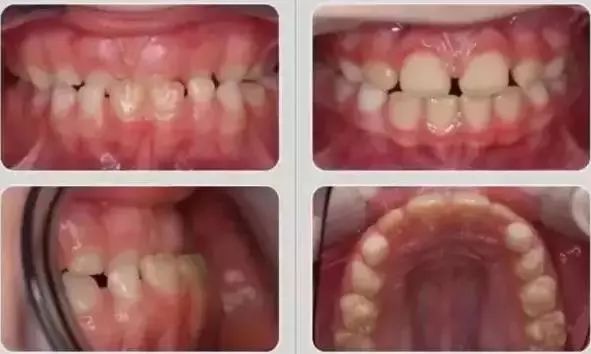

恒牙期效果对比